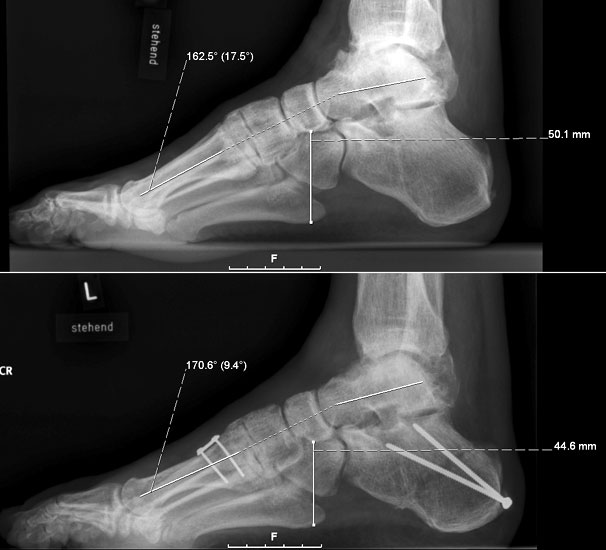

Dorsalflektierende Osteotomien des medialen Mittelfuβes (Abb. 6 – 9, Video 4)

• Erhöhter lateraler Talo-Metatarsale I Winkel (Meary-Winkel) als Ausdruck des plantarflektierten medialen Mittelfuβes, insbesondere im "forefoot driven hindfoot varus" (positiver Coleman block Test).

Die reduzierte Steilstellung des 1. Strahls wirkt sich positiv auf den Rückfuβ varus und den Vorfuβ adductus aus. Auch die relative Dorsalflexion des Talus in der Sprunggabel mit anterioren OSG-Impingement und verringerter OSG-Dorsalflexion wird verbessert.

Generell wird die dorsalflektierende MT I Osteotomie (Abb. 6 und 7) nicht isoliert ausgeführt, sondern ist Teil der gesamten Hohlfuβ-Korrektur. Beim absolut flexiblen Hohlfuβ ist sie gelegentlich zusammen mit einem Peroneus longus auf brevis oder einem Release der Plantarfaszie ausreichend. Diese Osteotomie ist einfach durchzuführen und hat eine geringe Pseudarthroserate.

Eine ähnliche dorsalflektierende Osteotomie des Os cuneiforme mediale (reversed Cotton Osteotomie, Abb. 8 und 9), ebenfalls mit Entnahme eines dorsal basierten Knochenkeils, ist effektiver im Ausmass der Korrektur, jedoch oftmals wegen der Insertion des kräftigen Lisfranc-Ligaments nur schwierig zu schliessen.